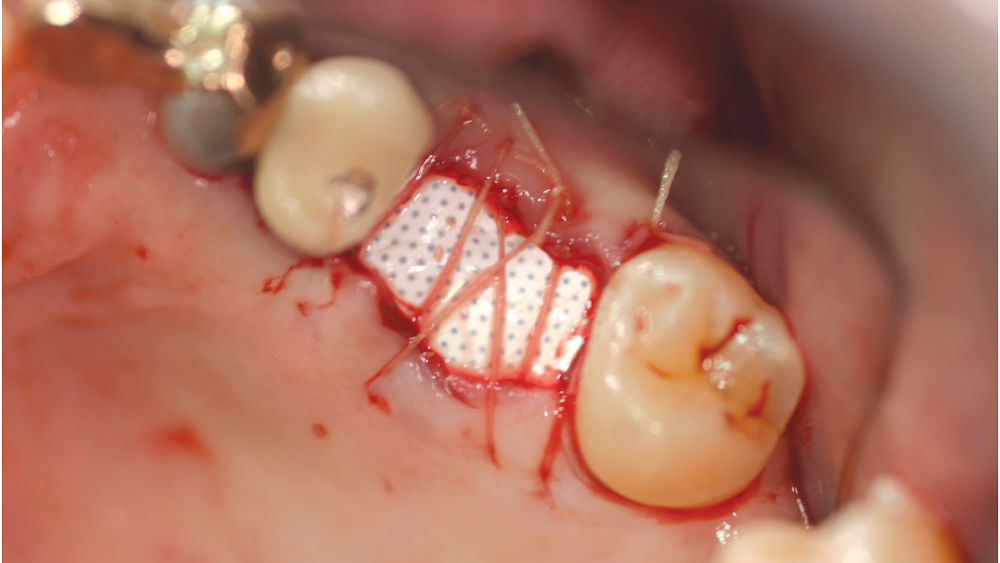

Titanium Mesh Membranes

Titanium mesh is a non-resorbable membrane that has been shown to be effective in maintaining space without collapsing. The membranes are flexible and can be bent and manipulated to form around the bony defect. The titanium mesh has demonstrated biocompatibility and features holes within the mesh, which allow for maintaining blood supply from the periosteum. The disadvantages of titanium mesh are increased wound dehiscence and difficulty in maintaining soft-tissue coverage (Figs. 4a, 4b). This may lead to increased infection and patient discomfort, which could lead to the necessity for early removal.

Figure 4a: Titanium mesh membranes have holes incorporated within the mesh

Figure 4b: Mesh exposure

Figures 4a, 4b: Titanium mesh membranes have holes incorporated within the mesh (4a), which allow for maintaining blood supply; however, these membranes have the disadvantage of increased wound dehiscence, which commonly involves exposure of the mesh (4b).